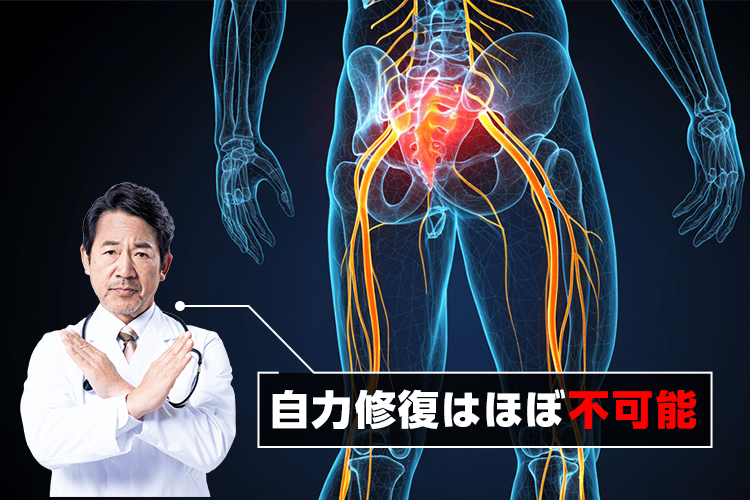

しかも残念なことに、

神経は一度損傷すると

自力で修復するのはほぼ不可能…

だから、

放置してても治ることはなく、

悪化すると寝たきりになる危険も😱

ちなみに

痛みどめの薬やマッサージ、整骨院は

"症状を緩和"することはできますが、

神経を修復することはできないため

根本治療にはなりません…

だから坐骨神経痛を根本解決するには

内側から神経を修復するしかないんです。